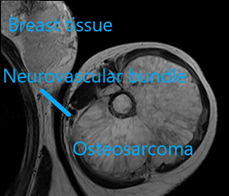

MRI scan

The MRI scan is important to differentiate sarcomas from infections and to evaluate soft tissue components, and the integrity of the neurovascular bundle. This is often a diagnostic modality which is performed at specialised centres.